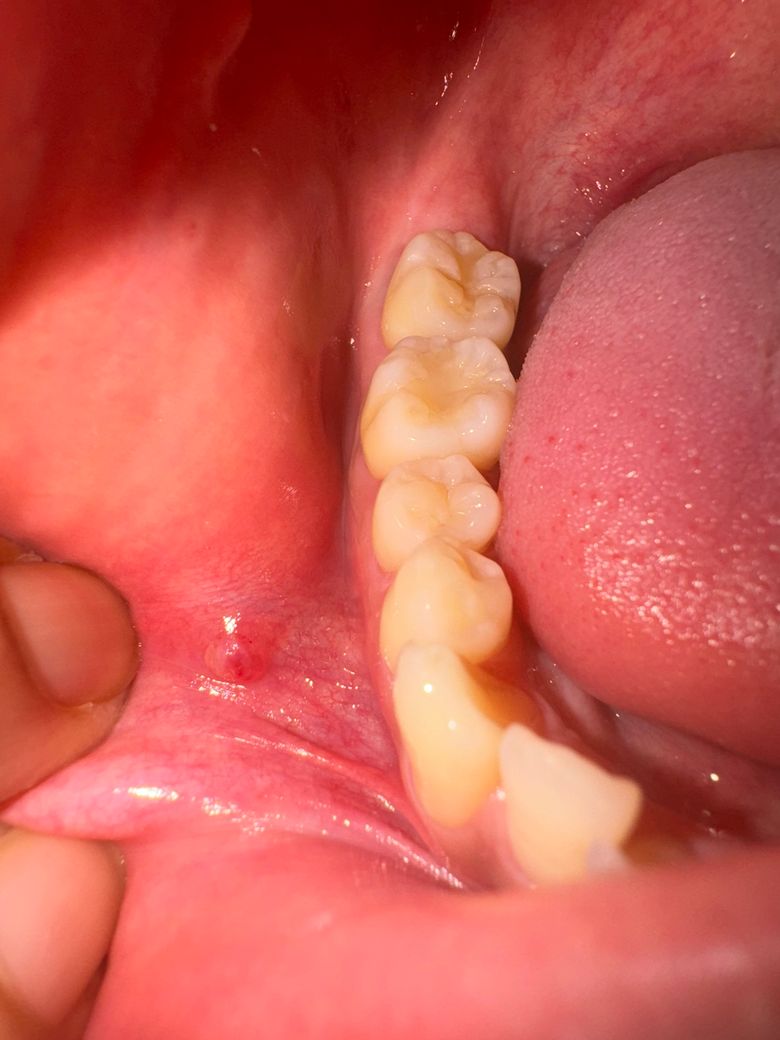

이렇게 변했다가 지금 생긴지 한달 반정도 되어가는데

겉은 아물었으나 전체적인 사이즈는 커진 느낌입니다.

• 3번 째 사진